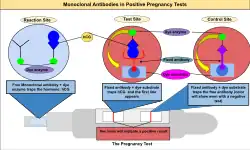

Identificada no início do século XX, a gonadotrofina coriônica humana (hCG) é um hormônio glicoproteico que aumenta rapidamente nas primeiras semanas da gestação, atingindo geralmente o pico entre 8 e 10 semanas de idade gestacional.[4][5] O hCG é produzido pelo que se tornará a placenta.[6] A testagem pode ser feita por meio de amostra de sangue (soro) — geralmente em ambiente médico — ou com urina, que pode ser realizada em laboratório ou em casa. Os ensaios usados para detectar a presença de hCG no sangue ou na urina são, em geral, confiáveis e baratos. A secreção do hCG pode ocorrer já seis dias após a ovulação, em média entre 8 e 10 dias após a ovulação; este é o período mais precoce em que o hCG pode ser detectado no sangue.[7][5][8] A concentração de hCG no sangue é mais alta que na urina; portanto, um exame de sangue pode ser positivo mesmo quando o de urina ainda é negativo.[9][10] Testes qualitativos (resultados sim/não ou positivo/negativo) verificam a presença da subunidade beta da gonadotrofina coriônica humana no sangue ou na urina. Para um teste qualitativo, os limites para um resultado positivo são geralmente determinados por um valor de corte de hCG no qual pelo menos 95% das mulheres grávidas teriam um resultado positivo no dia do primeiro atraso menstrual.[11] Testes qualitativos de urina variam em sensibilidade. Testes de alta sensibilidade são mais comuns e geralmente detectam níveis de hCG entre 20 e 50 miliunidades internacionais/mL (mUI/mL). Testes de baixa sensibilidade detectam níveis de hCG entre 1500 e 2000 mUI/mL e têm aplicações clínicas específicas, como a confirmação do sucesso de um aborto medicamentoso.[12] Testes qualitativos de urina disponíveis para uso doméstico são normalmente projetados como teste de fluxo lateral.

Outro kit de teste de gravidez caseiro foi baseado no trabalho de Judith Vaitukaitis e Glenn Braunstein, que desenvolveram um ensaio sensível de hCG no Instituto Nacional de Saúde dos Estados Unidos.[44][45] Esse teste chegou ao mercado em 1978.[46] Na década de 1970, a descoberta dos anticorpos monoclonais levou ao desenvolvimento de imunoensaios relativamente simples e baratos, como testes baseados em inibição por aglutinação e ELISA sanduíche, usados em testes caseiros modernos de gravidez. Os testes agora são tão baratos que podem ser produzidos em massa e usados até em publicidade.[47]